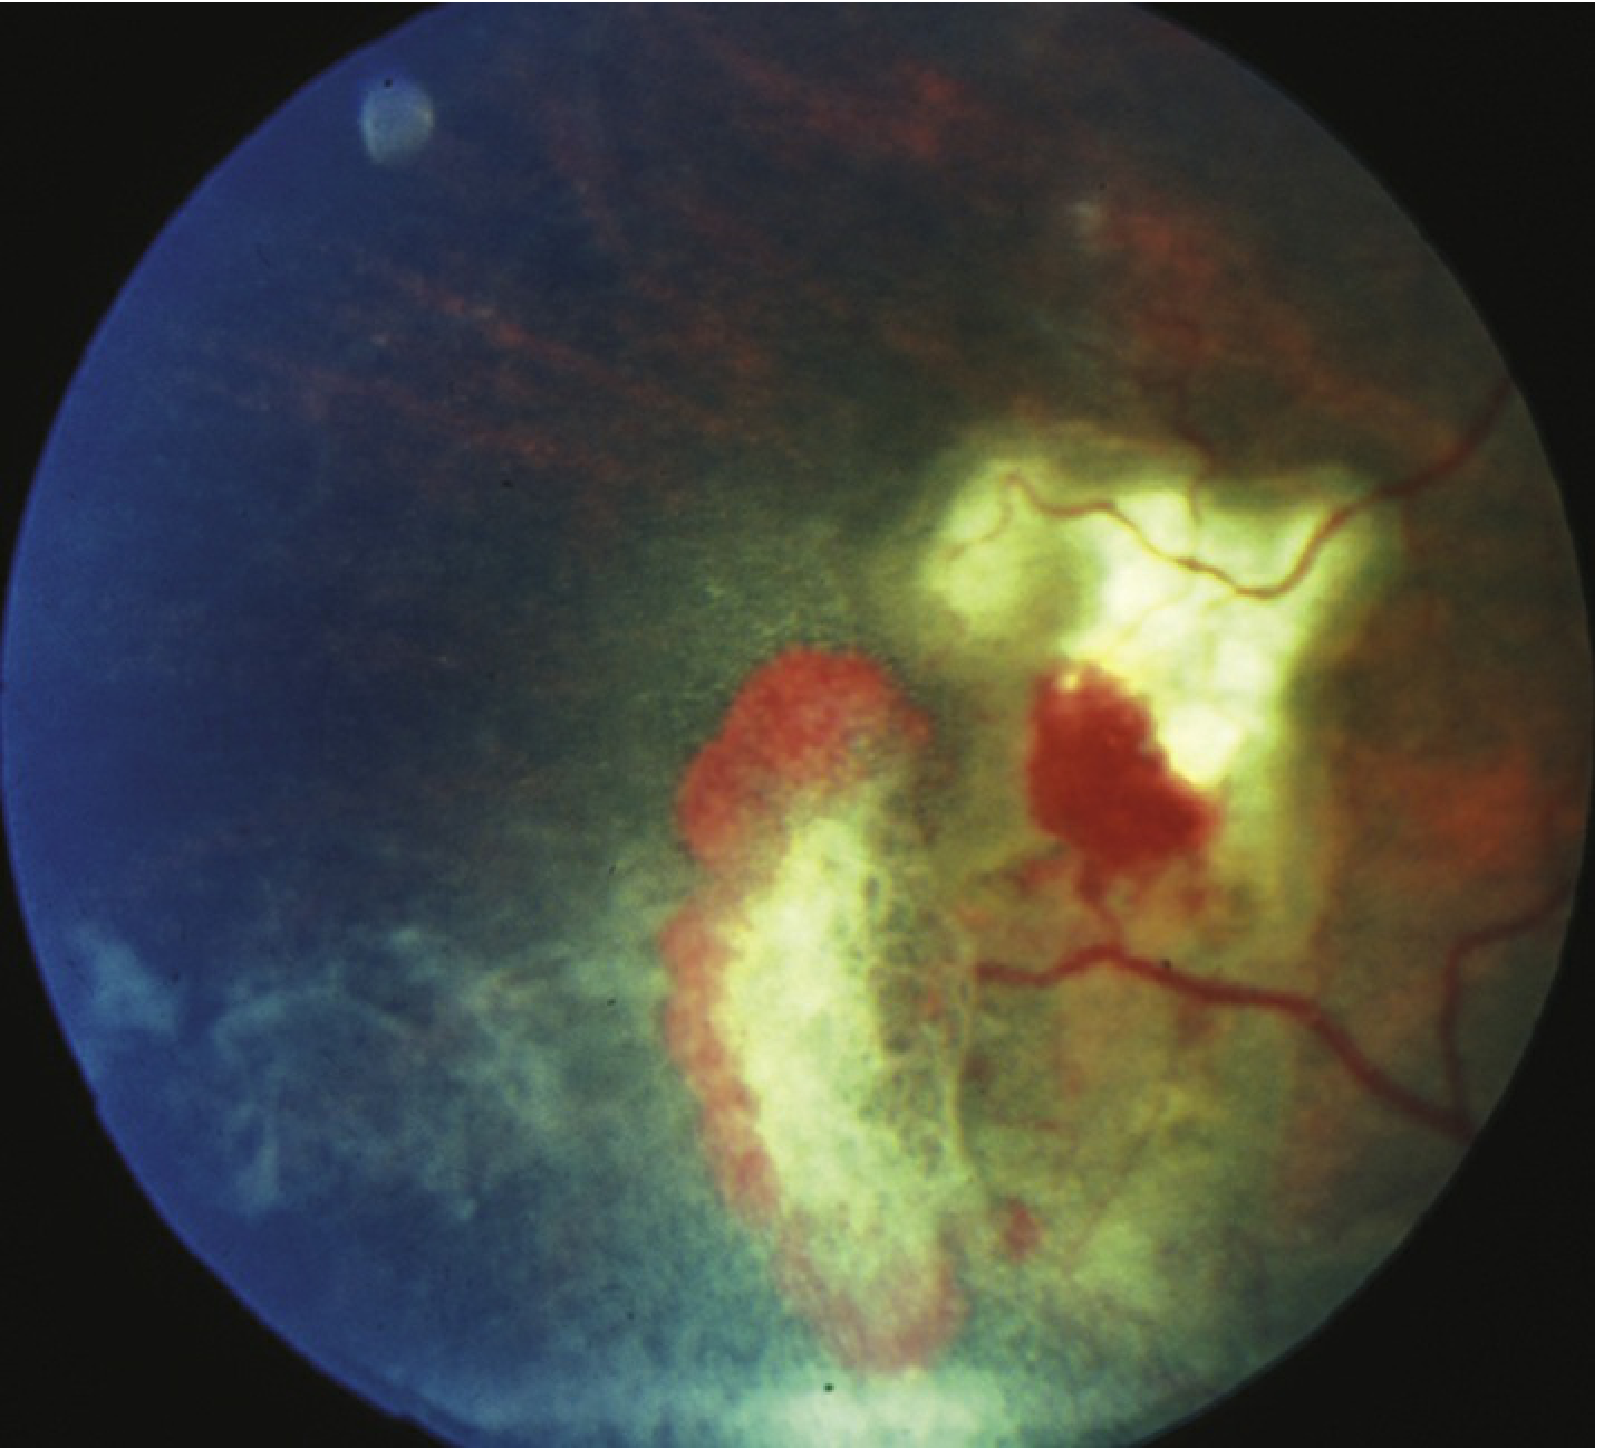

Fig. 1 — Sickle cell retinopathy: sea fan neovascularization with vitreous haemorrhage (Wills Eye Manual)

Sea fan neovascularization with vitreous haemorrhage

4Vitreous haemorrhage from the NV

Fundus angiography (FA) in stage 3: sea fan filling and peripheral capillary non-perfusion in early phase → leakage from NV in late phase. Wide-field imaging is particularly well-suited to evaluation.